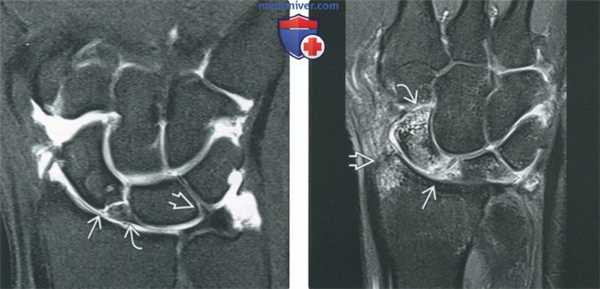

(Слева) Непрямая МР-артрография в режиме Т2 ВИ FS, коронарный срез: визуализируется травматический разрыв ТФХК, проявляющийся отрывом волокон от ямки и шиловидного отростка с появлением жидкости во влагалище сухожилия ЛРЗ.

(Справа) Непрямая МР-артрография в режиме Т2 ВИ FS, аксиальный срез, этот же пациент: на ладонной поверхности запястья определяется синовиальная киста в Отмечается наличие жидкости во влагалище сухожилия ЛРЗ. (Слева) Рентгеноскопия, передне-задняя проекция: визуализируется поступление контрастного препарата в ДЛЛС через центральную часть ТФХК, что свидетельствует о глубоком разрыве последнего.

(Справа) МР-артрография в режиме Т1ВИ FS, коронарный срез: наблюдается разрыв центральной мембранозной части ТФХД. Контрастный препарат распространяется в ДЛЛС. Дефект в данном месте обычно возникает вследствие дегенеративного процесса. (Слева) МР-артрография в режиме Т1ВИ FS, коронарный срез: отмечается, что распространение контрастного препарата ограничено лучезапястным суставом, а верхний край ТФХК имеет ровный контур. Пациент жалуется на боли с локтевой стороны запястья после падения.

(Справа) МР-артрография в режиме Т2ВИ FS, коронарный срез, этот же пациент: визуализируется неровный контур глубокого слоя ТФХК, обусловленный его разрывом. В ДЛЛС видна собственная жидкость, а не контрастный препарат, поскольку она характеризуется гипоинтенсивным сигналом на Т1 ВИ.